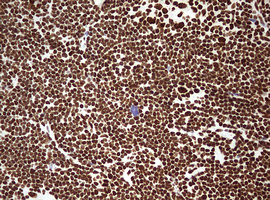

Immunohistochemical staining of paraffin-embedded Human lymphoma tissue using anti-HNRNPM mouse monoclonal antibody. (Heat-induced epitope retrieval by 10mM citric buffer, pH6.0, 120°C for 3min, M06017-2)